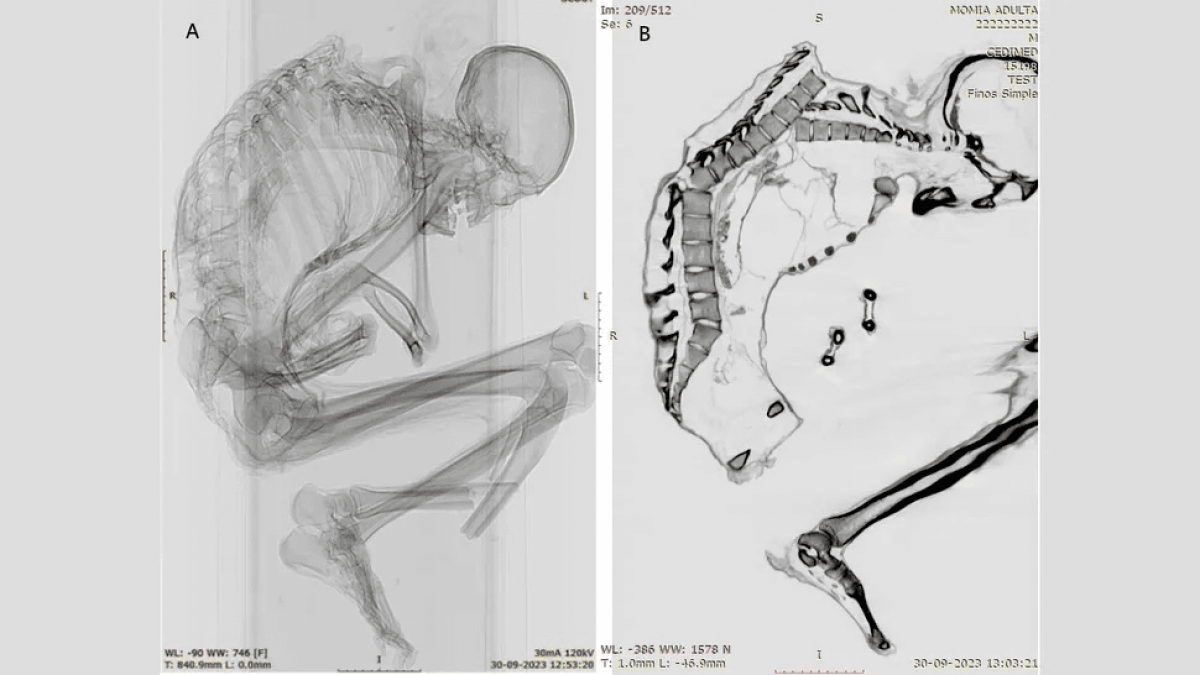

Каталина Моралес и Франсиско Гарридо, археологи из Национального музея естественной истории в Сантьяго, использовали компьютерную томографию и рентгеновские снимки, чтобы выявить мельчайшие детали обширной травмы, которая, вероятно, привела к смерти мужчины. Они сообщили:

По словам ученых, на верхней части позвоночника мужчины были обнаружены многочисленные незажившие переломы. У него также были переломы ребер, лопатки и ключицы, что указывает на "сильный удар по обширной области" верхней части спины, показывая, что "верхняя левая часть грудной клетки приняла на себя основной удар". Удар сместил несколько позвонков и разрушил грудную клетку.

Кроме того, исследователи обнаружили перелом у основания позвоночника, который был результатом первоначальной травмы верхней части спины. Они написали:

Важно, что на черепе, шее и руках мужчины не было обнаружено никаких повреждений, что указывает на то, что удар произошел, когда мужчина находился в положении головой вниз. Возможно, он активно занимался добычей полезных ископаемых или пытался защитить голову руками, когда на него упал тяжелый предмет сверху. Подобные травмы наблюдаются у людей, пострадавших от землетрясений, а также при производственных травмах в лесной, строительной и горнодобывающей промышленности.